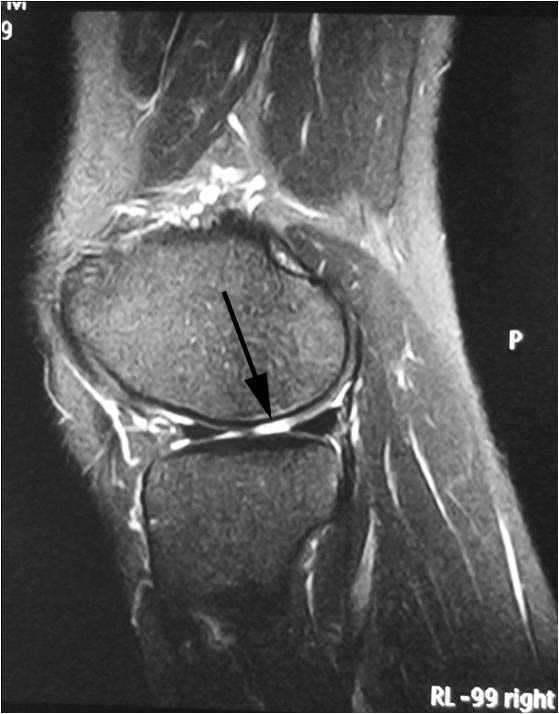

Sure. This is a person who has pain in the right knee after when playing tennis. MRI scan showed a full thickness cartilage defect (or torn cartilage) in the lateral (outer) femoral condyle.

This is how it looks like during arthroscopy:

The torn cartilage was found floating inside the knee. Sometimes it cannot be found.